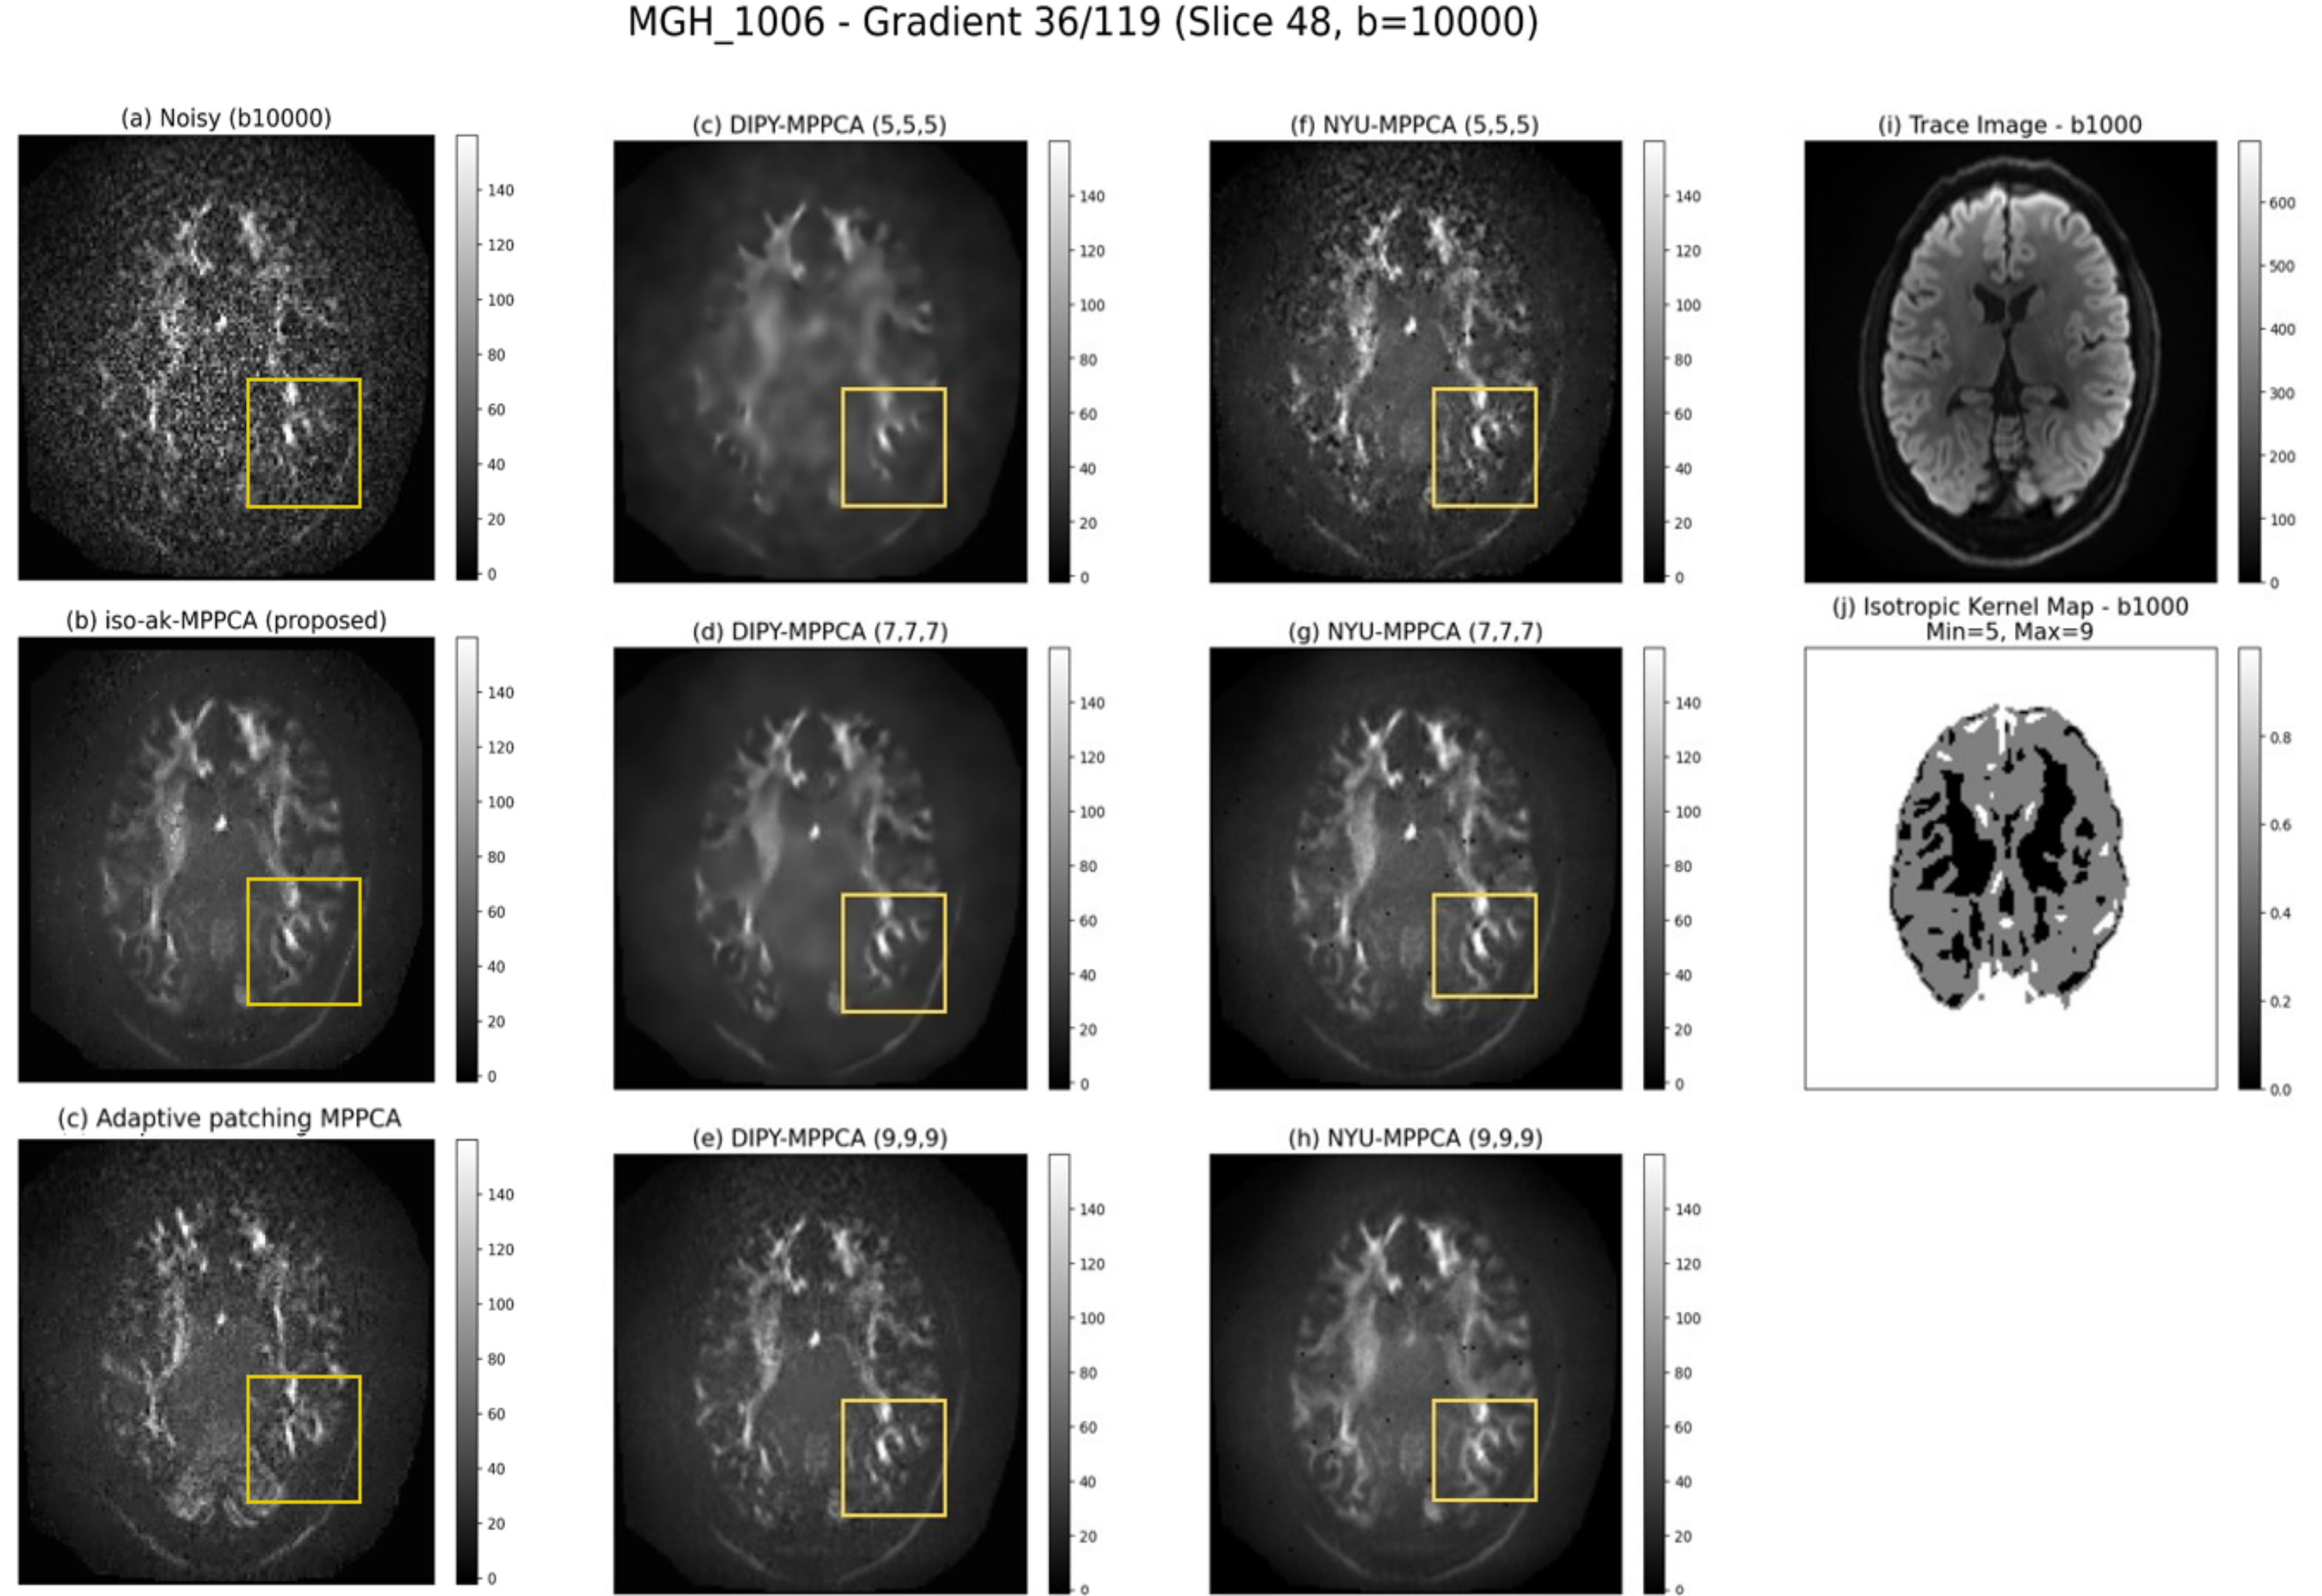

Three subjects from the HCP (MGH-USC) dataset [8] were analyzed: MGH-1005, MGH-1006, MGH-1010. Denoised DWI results are shown in Figure 1. For MGH-1010 and MGH-1006, DWI data with was used, while for MGH-1005, results are shown for . The primary diffusion directions for the noisy and denoised (using proposed method) DWI data are represented using a red-green-blue representation to create a directionally encoded color (DEC) map (color FA maps) in Figure 2 [7, 9]. As shown in Figure 1, the NYU-MPPCA and DIPY-MPPCA denoised DWI data depends on the kernel size choice (a hyperparameter to be optimized). In contrast, the proposed method estimates voxel-wise kernel sizes based on local structural information (refer Section 2.1). The corresponding kernel size maps are also shown in Figure 1. These maps reveal that regions with high structural detail are assigned smaller kernel sizes, helping preserve fine features and reducing the risk of blurring during denoising. Although the adaptive patching MPPCA [6] addresses structural blurring to some extent, it does not suppress noise as effectively. Among the compared methods, the proposed approach demonstrates superior performance in preserving anatomical structure while effectively reducing noise in DWI data. As observed from the color FA maps in Figure 2, the proposed method improves the clarity of these maps, resolving noisy regions and preserving meaningful diffusion direction information.

All evaluations in this study were conducted using data from the Human Connectome Project (HCP) (MGH-USC) [8]. The proposed denoising method was applied to DWI datasets with -values of 10000 and 5000 across three subjects. Comparative performance was assessed against publicly available implementations of MPPCA. Specifically, NYU-MPPCA refers to the implementation by Veraart et al. [1], DIPY-MPPCA refers to the version by Garyfallidis et al. [7]. The adaptive patching variant from the DESIGNER toolbox [6] was also included for fair comparison. Both NYU-MPPCA and DIPY-MPPCA implementations require a fixed kernel size for denoising. In this study, we applied isotropic kernel sizes of 5, 7, and 9 for these two methods. For the proposed ak-MPPCA, the kernel size estimation limits were set to .

The MPPCA implementation is updated to consider the estimated kernel size for patch based denoising across the voxels. The remaining aspects of MPPCA denoising, such as noise estimation and signal thresholding is maintained as discussed in Veerart et al. [1]. In this work, we set and to 5 and 9 respectively.